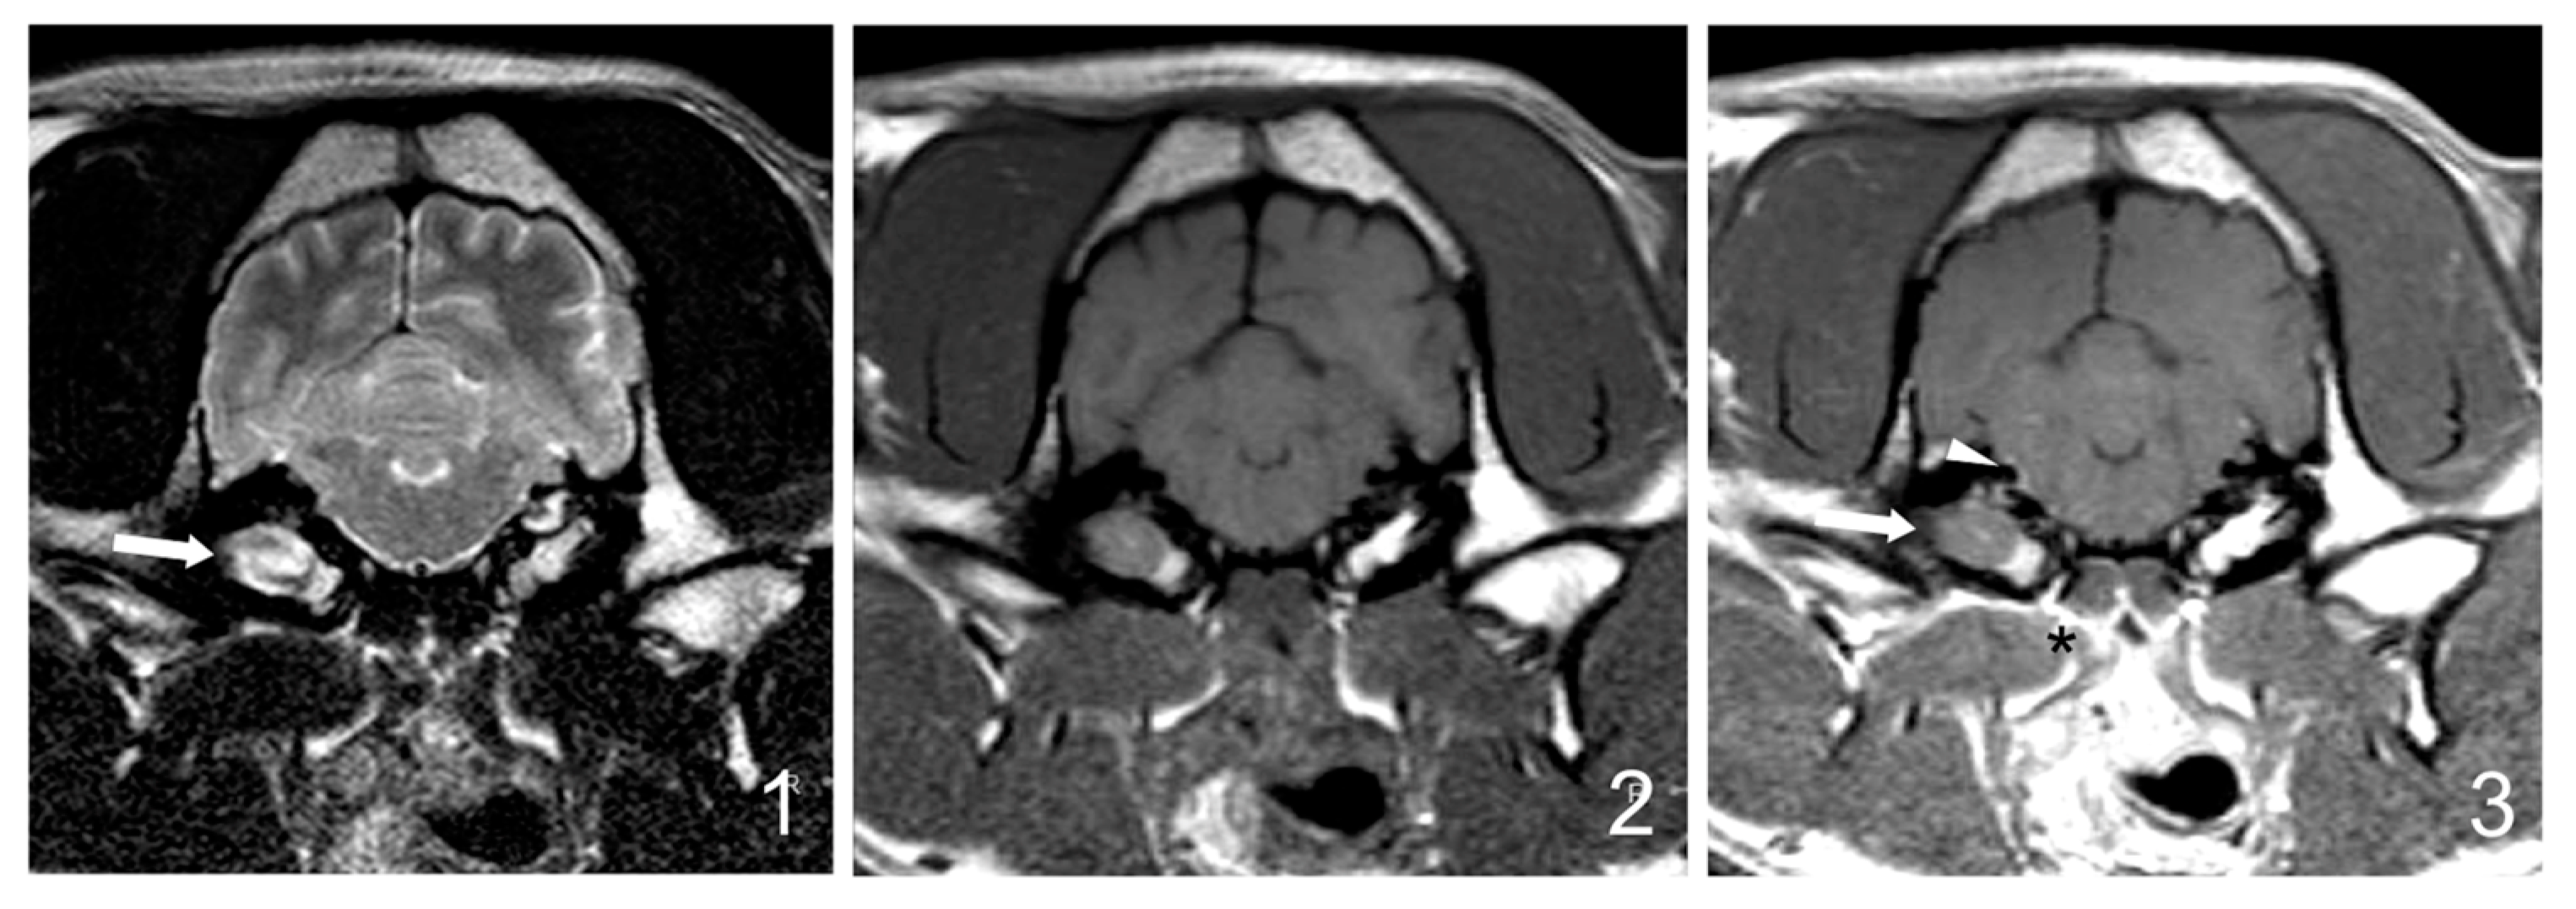

If performed, follow-up MRI results were studied. Good radiological improvement was considered if the tympanic cavities occupation was reduced by 25% or greater, there was no soft tissue enhancement, and/or no signs of abscess or empyema if it was previously present.

Follow-up MRI studies (5/30) were performed from 5 weeks to 6 months after treatment initiation and included three dogs from group B (3/17 dogs, 17%) and two dogs from group C (2/7 dogs, 28%). Radiological improvement was noticed in all dogs. No signs of the previously observed epidural material or soft tissue enhancement were detected. In four dogs, a decrease (up to 50%) in the occupation of the tympanic cavities was observed, even though some degree of content was still present (Figure 4).

Figure 4. Follow-up MRI images (1: transverse T2W, 2: transverse T1W, 3: transverse T1W after gadolinium administration at the level of the tympanic bullae) of the 9-year-old French bulldog from Group C shown in Figure 1, after medical treatment (enrofloxacin and TS for 12 weeks). The brainstem occupation (black arrowheads in Figure 1 [C1 and C3]) is not visible, and the degree of contrast enhancement in surrounding soft tissues (black asterisk) and meninges (white arrowhead) is mild and focal compared to the previous MRI. No significant changes in the bullae occupation are observed (white arrow).